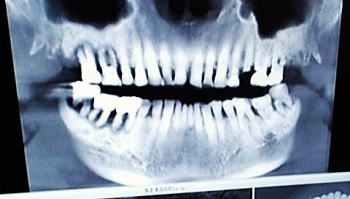

![]() 原始的記録媒体だって! (2025年6月6日早川歯科X線正面) |

![]() 骨だけになった仙人! (2025年6月6日早川歯科X線右側面) |